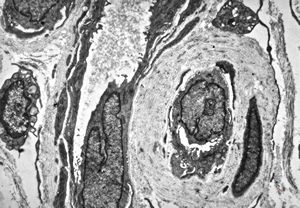

F,48y. | reduplication of endothelial basement membranes - skin - susp. lupus erythematodes